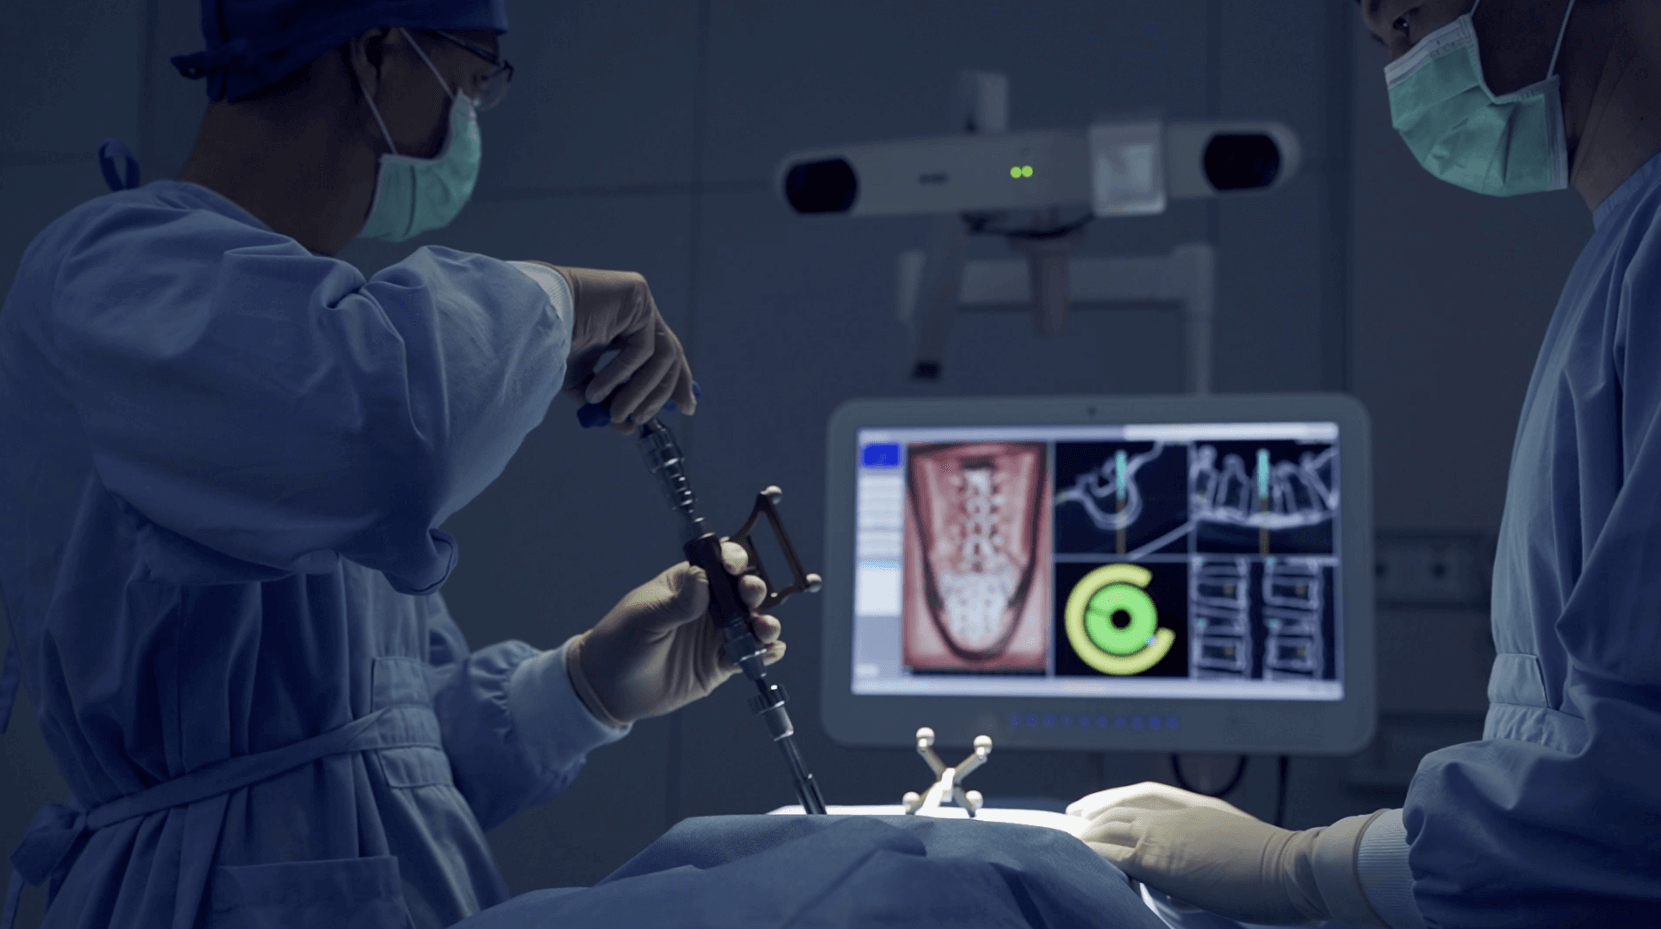

Minimally Invasive Surgery (MIS) is central to Dr. Ashana’s approach, enabling treatment of complex spinal conditions through advanced techniques that use smaller incisions and cause less disruption to surrounding tissues. By preserving muscles and soft tissue, these methods reduce postoperative pain, minimize scarring, and promote faster recovery. Dr. Ashana combines safety, precision, and advanced technology to achieve optimal outcomes, helping patients return to normal activities sooner.

Minimally invasive spine surgery is not a single procedure—it is a fundamental approach by which Dr. Ashana performs every surgery.

Rather than relying on large incisions and muscle disruption, minimally invasive techniques allow spine conditions to be treated with smaller incisions, less tissue damage, and greater precision.

To perform minimally invasive spine surgery, Dr. Ashana utilizes advanced tools and technologies including: